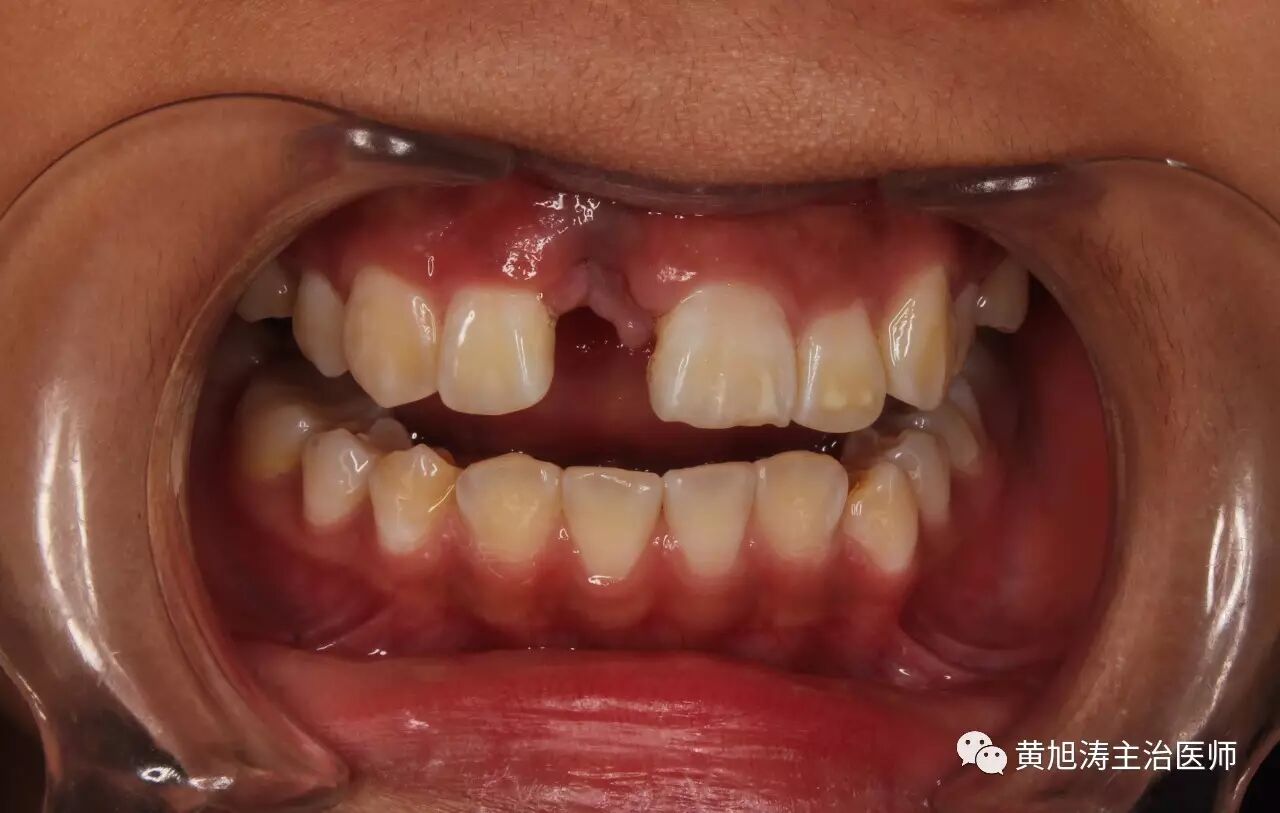

这个时候就有帅哥美女死活不同意了,让我3个月没有牙齿,你让我如何出门,倒不如死了算了。

做个临时的假牙,每天晚上睡觉前拿出来,早上起床的时候再戴上,既解决了美观问题,又不留下后遗症

等到3个月到了,我们再做永久性镶牙,那个时候就可以美美的啦